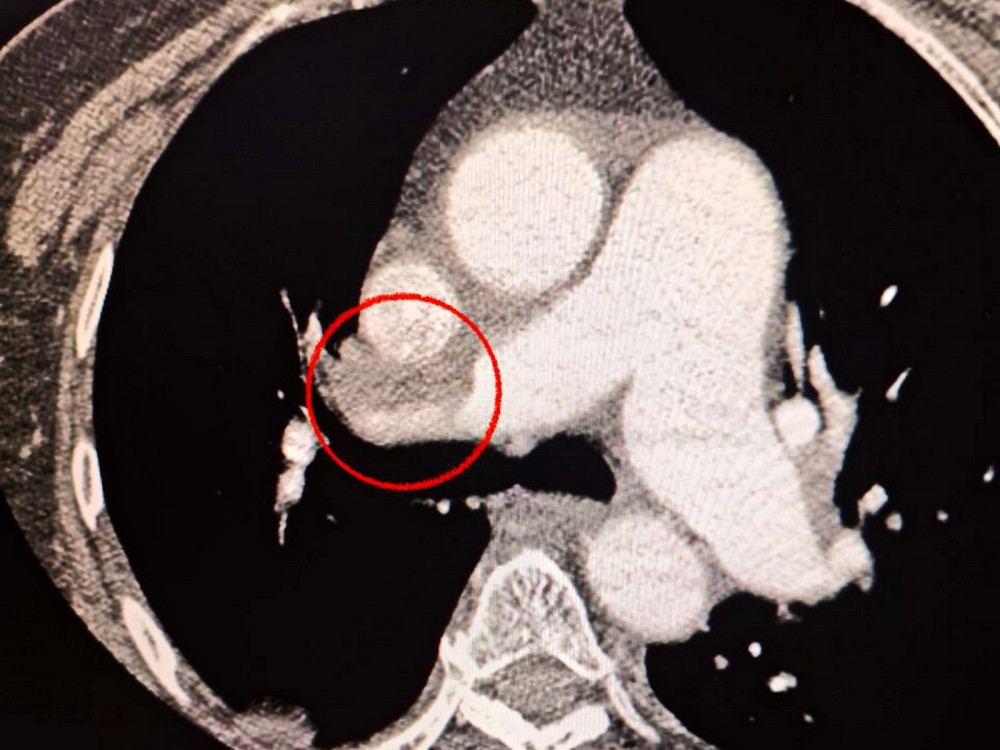

Пацієнтка була доставлена до лікарні з серйозним інсультом. Під час діагностики за допомогою комп'ютерної томографії лікарі виявили закриття середньої мозкової артерії.

Також лікарі помітили, що жінка має проблеми з диханням, тому вони провели додаткове обстеження легень, що підтвердило наявність тромбоемболії.